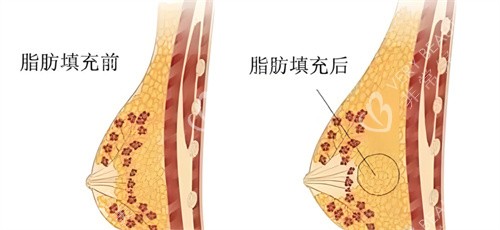

在填充时,医生要将脂肪均匀地注射到胸部各个层次,让脂肪能够充分接触到周围的组织,获取养分,这样才能提高存活率。